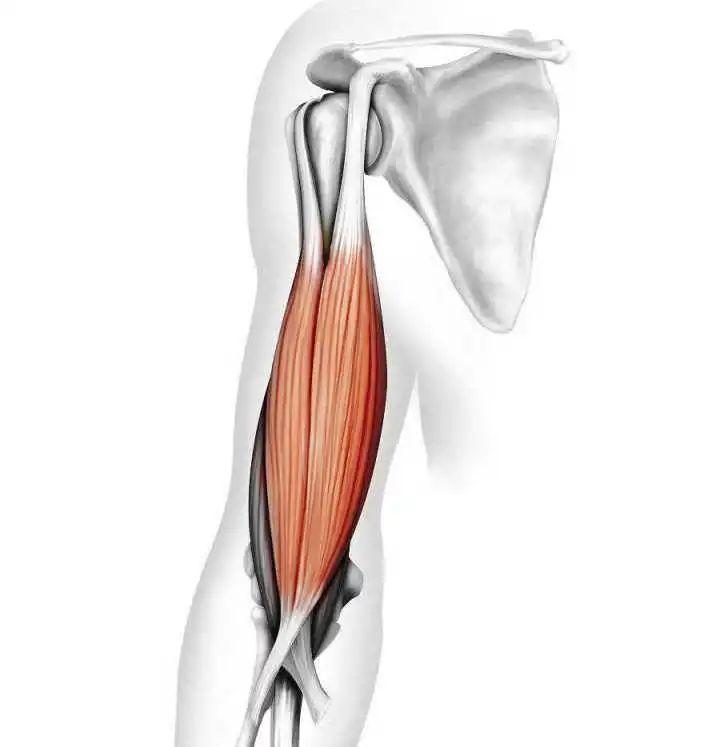

肱二头肌长头腱鞘炎

肱二头肌为屈肘主要肌肉,而长头走形复杂,有长长的腱鞘,容易反复摩擦、脱位等。该部位易产生疼痛,疼痛主要局限为肩前,屈肘疼痛加重。